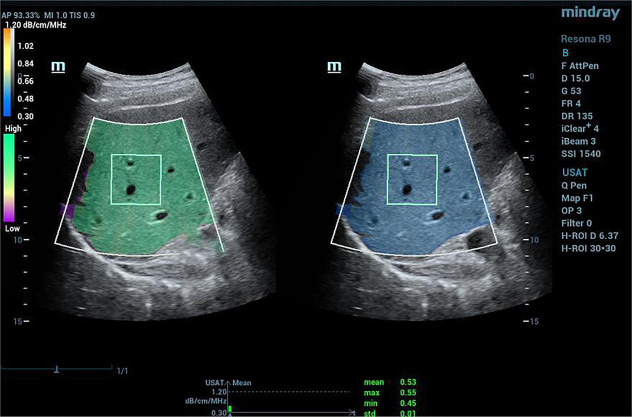

Background: Thyroid hormones impact on metabolic homeostasis, and low thyroid hormone levels, both systemically and hepatically, have been linked to hepatic steatosis. However, prior studies in this area often lacked quantification of steatosis. Ultrasound attenuation analysis (USAT) is a novel imaging technique for hepatic steatosis detection based on the attenuation coefficient. Our objective in this study was to assess the correlation between thyroid hormone levels and hepatic steatosis via the USAT attenuation coefficient in metabolic dysfunction-associated steatotic liver disease (MASLD) and chronic hepatitis B (CHB) groups.

Methods: This retrospective study included 86 patients with CHB and 45 patients with suspicious MASLD. Demographic information, biochemical parameters, and thyroid hormone levels were analyzed. The severity of steatosis in MASLD or CHB was assessed by USAT.

Results: Patients in the MASLD group were more likely to have type 2 diabetes mellitus (T2DM) and hypertension as compared with those in the CHB group (P<0.05). The levels of triiodothyronine (T3) were significantly lower and the platelet counts higher in the MASLD group than in the CHB group (P<0.05). The body mass index (BMI), distance from skin to capsule, USAT values, and alanine aminotransferase (ALT) and aspartate aminotransferase (AST) levels in patients with hepatic steatosis were significantly higher than those in patients without hepatic steatosis (P<0.05). Logistic regression analysis indicated a correlation between free triiodothyronine (FT3) level and hepatic steatosis (P=0.04) as well as between free thyroxine (FT4) level and hepatic steatosis (P=0.045).

Conclusions: Quantitative USAT evaluation suggested that hepatic steatosis is strongly correlated with thyroid hormones. These data emphasize the relevance of thyroid hormones for regulating hepatic lipid accumulation and metabolism.